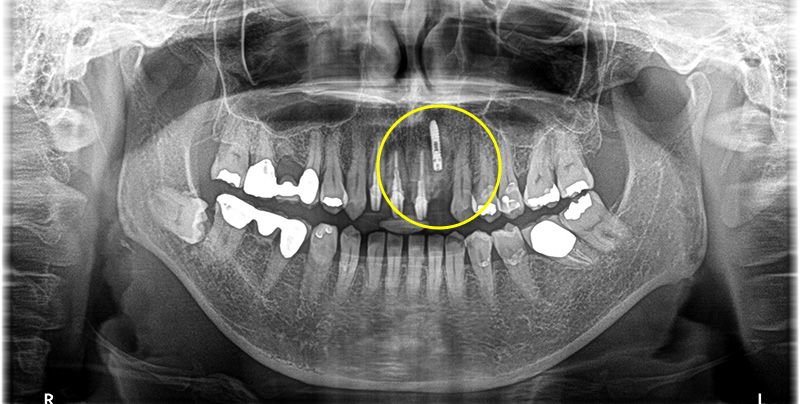

レントゲンでの検査の結果、左上2番目の歯の根に感染が起こっており、膿が溜まっていたため痛みが出ていたと診断しました。

CT写真にて確認したところ、膿がかなり大きく、治療しても完治が難しいため患者さまと相談し、成功率が高いインプラントでの治療をご希望されました。

抜歯窩を確認すると、膿が大きく唇側に穴が開いていることが確認できます。

骨欠損の範囲が大きかったため骨造成も同時に行いました。